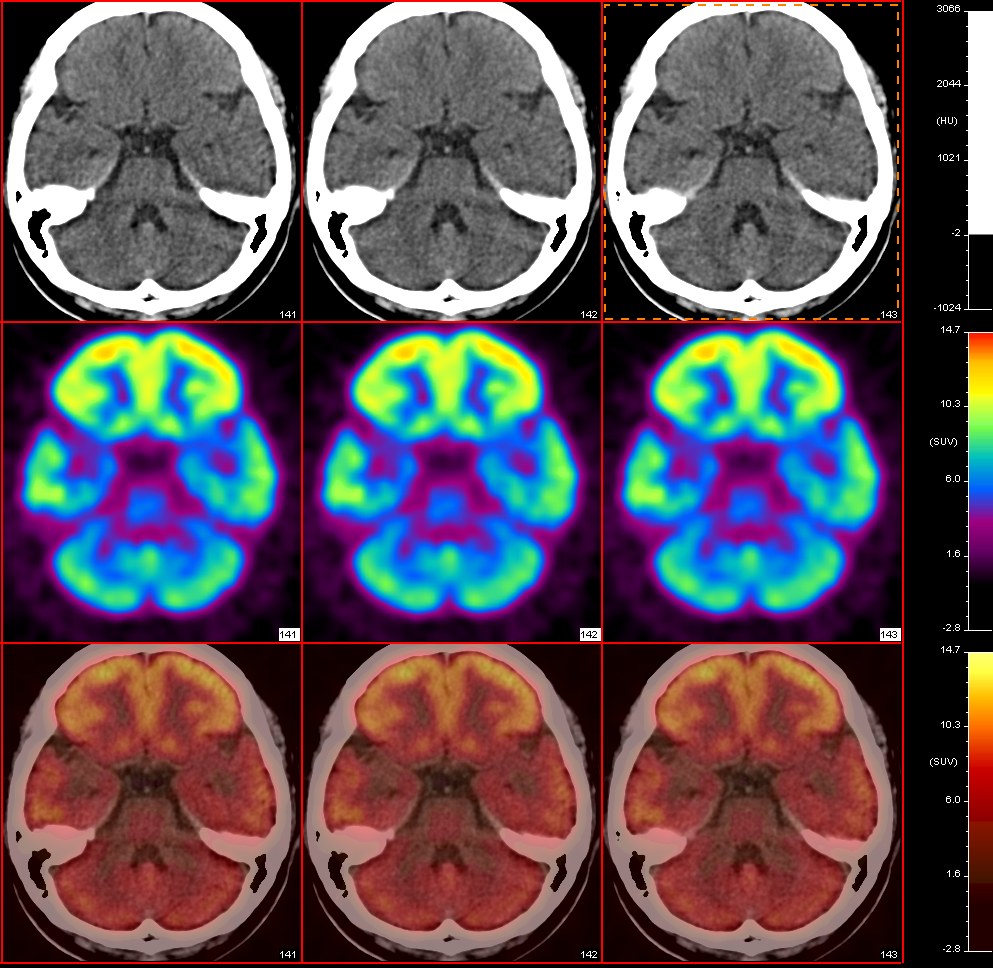

颞叶癫痫术前定位

患者,女性,22岁

自1岁起反复癫痫发作

先后服用苯妥英钠、卡马西平治疗,效果不佳

海马MRI示:双侧海马体积缩小,信号异常

拟行外科手术治疗

PET/CT示:

癫痫发作间期,右侧颞叶FDG代谢减低,考虑病灶位于右侧颞叶